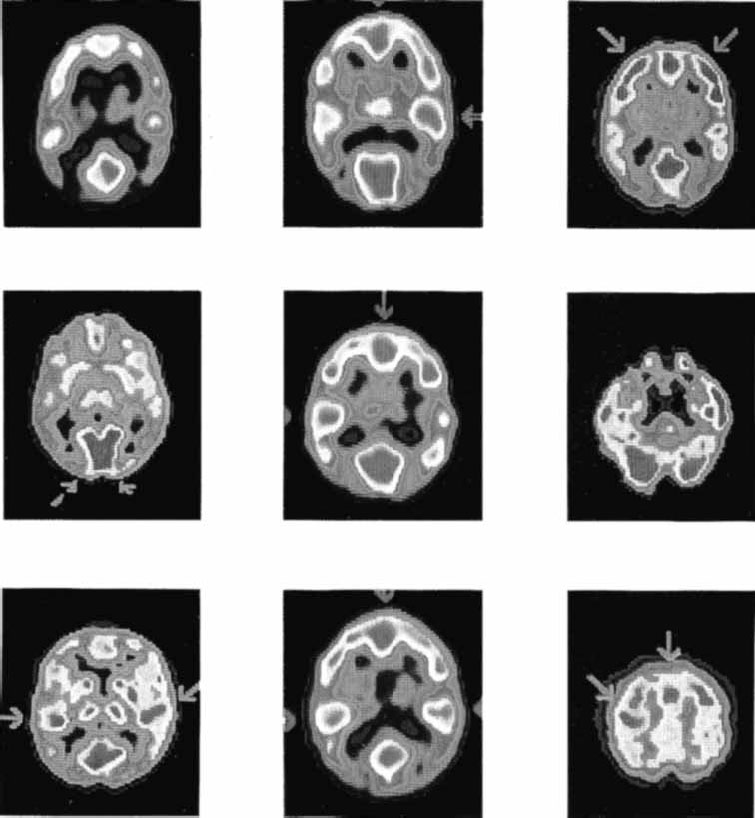

Рис. 2.15. Снимки мозга больных, перенесших инсульт на правой половине мозга, полученные с помощью метода компьютерной томографии (Carlson, 1992).

Для улучшения качества изображения перед исследованием пациенту вводят контрастное вещество. Особенно эффективна компьютерная томо графия для исследования повреждений мозга, например, вследствие инсульта (рис. 2.15), рассеянного склероза, опухолей. Кроме очевидной необходимости этого метода для хирургического исследования перед операциями он представляет значительный интерес для психофизиологов и нейрофизиологов, которые изучают когнитивные процессы и поведение людей, имеющих повреждения мозга.